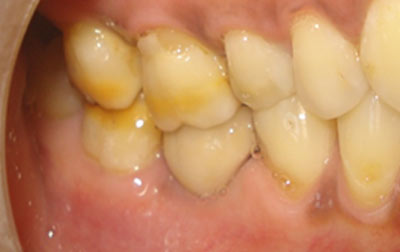

Dental laminates closely resemble dental veneers and are becoming a preferred choice for enhancing smiles. Available in composite or porcelain, these thin, customized shells offer numerous advantages. They effectively mask stains and discolorations on individual teeth, especially when conventional teeth-whitening methods fall short. In cases of stubborn and deep dental stains caused by factors like excessive fluoride or certain medications, standard whitening procedures often prove ineffective. Dental laminates step in as a promising solution, especially with lighter-colored variants effectively concealing teeth with severe discoloration.

Beyond staining, laminates address unexpected dental issues such as chips, wear, or breakage. They swiftly camouflage imperfections, whether on a single tooth or multiple ones, revitalizing the overall dental aesthetic. Dental laminates also serve as a corrective measure for uneven, misaligned teeth, as well as indentations and protrusions. A minor enamel trim enhances the adherence of these thin shells while preventing overcrowding and closing gaps between teeth. With the ability to seamlessly match natural tooth shades, dental laminates seamlessly integrate into the oral environment. Patients even have the flexibility to select their desired level of tooth whiteness.

Notably, the effects of dental laminates are enduring, eliminating the need for subsequent adjustments or reshaping. In essence, dental laminates offer a versatile and lasting solution for an array of dental imperfections, yielding confident smiles without the constraints of staining, damage, or misalignment.